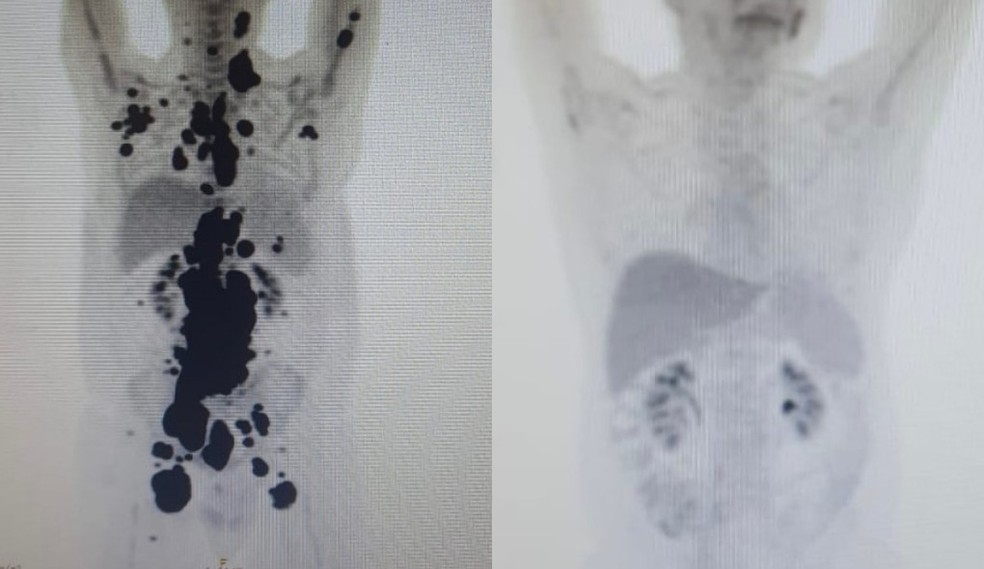

No caso de Paulo, uma tomografia feita antes e depois do tratamento, mostram como o uso do CAR-T Cell fez total diferença no processo de cura do paciente.

“Quando a gente viu, todo mundo vibrou. Coloquei no grupo de professores titulares da USP e todo mundo ficou impressionado ao ver a resposta que ele teve”, disse Vanderson Rocha, coordenador nacional de terapia celular da rede D’Or e professor da USP.